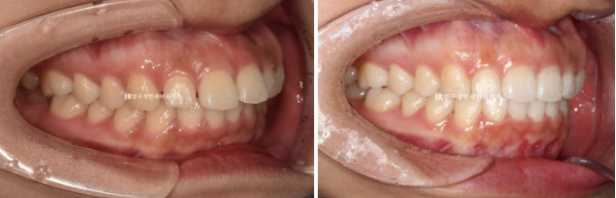

24.02

앞니 좌우 높낮이가 다른 것이 보입니다.

어금니 교합은 좋습니다.

이렇게 어금니 교합이 좌우 I급이면 인비절라인 라이트의 완벽한 적응증입니다.

앞니 사이 벌어진 공간을 모으고 약간의 치간삭제를 동반하여 돌출감도 어느정도 해결하는 것을 목표로 삼았습니다.

인비절라인 라이트 권유드렸고 2월에 장치 오더 그리고 3월부터 1단계 장치를 끼기 시작했습니다.

24.06

첫번째 세트 장치 14개를 다 낀 후 모습입니다.

모든 것이 좋지만 디테일한 것들을 좀 더 개선하기 위해서 추가장치 제작에 들어갔고 7월부터 10월까지 3개월간 장치를 더 낀 후 마무리 하였습니다.

24.10

24.02~24.10

뻗쳐있던 앞니 각도는 좋아졌고